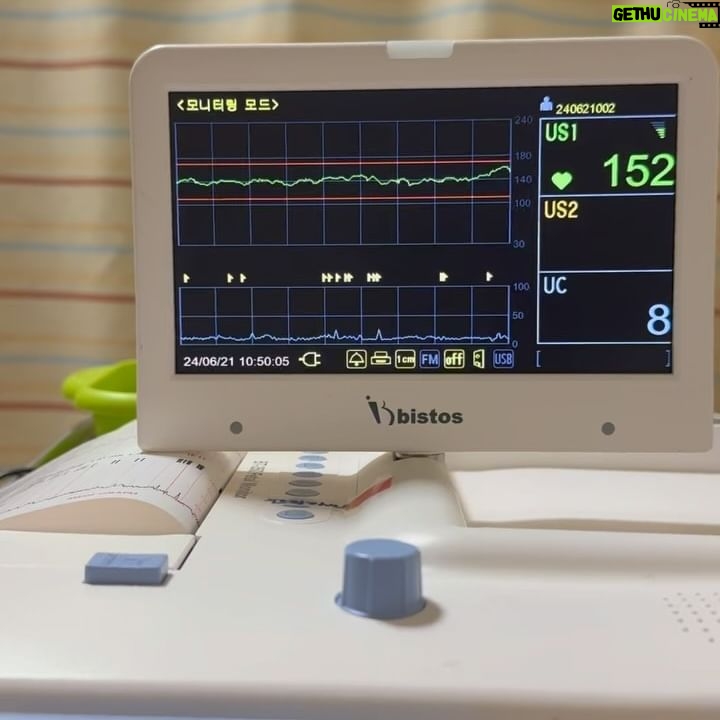

722 Likes – Kim Min-jung Instagram

Caption : . 첫째에게 곧 동생이 태어날 거라는 걸 알려주고 있어요 🙂 임신 초기부터 꾸준히 동생의 존재에 대해 이야기해줬는데 출산을 앞두니 더 마음이 쓰여요~ 출산하면 며칠 엄마랑 떨어져있어야 하니까 아인이도 미음의 준비 할 수 있게 일부러 병원도 같이 가고 상황을 이해할 수 있도록 노력하고 있어요ㅎㅎ 엄마 배 속에서 동생 심장이 콩콩 뛰고 있어~ 배 위에 가만히 손 올리면 꿈틀꿈틀 움직이지? 콩콩이는 누나가 정말 좋대~! 곧 뿅! 하고 태어날거야~ 동생 태어나면 자기가 다 알려줄거라며 기대하고 있어요ㅎ 아인이가 맘마도 주고 옷도 입혀줄거래요ㅋㅋ 인형으로 맹연습중ㅋㅋㅋㅋㅋ#과연 ㅋㅋㅋ 자꾸 자기 배 속에도 콩콩이가 있다고..손 대보라고.. 움직인다며 자기가 배 움직여요🤣 #태동 이 꽤 인상적이었던 듯.. 산부인과 다녀와선 자꾸 엄마 누우라고.. 담요 덮어주더니 배에 풀칠해야한다며 아인이가 콩콩이 보여줄게요~ 하네요ㅋㅋ 초음파 젤이 풀로 보였나봐요🤣🤣🤣 #병원놀이 의 진화 아인이 누나~ 잘 부탁해! . . #출산임박#태동검사#애둘맘#맘스타그램 #첫째#딸 이젠#누나 #아기가누나가되네Likes : 722

722 Likes – Kim Min-jung Instagram

Caption : . 첫째에게 곧 동생이 태어날 거라는 걸 알려주고 있어요 🙂 임신 초기부터 꾸준히 동생의 존재에 대해 이야기해줬는데 출산을 앞두니 더 마음이 쓰여요~ 출산하면 며칠 엄마랑 떨어져있어야 하니까 아인이도 미음의 준비 할 수 있게 일부러 병원도 같이 가고 상황을 이해할 수 있도록 노력하고 있어요ㅎㅎ 엄마 배 속에서 동생 심장이 콩콩 뛰고 있어~ 배 위에 가만히 손 올리면 꿈틀꿈틀 움직이지? 콩콩이는 누나가 정말 좋대~! 곧 뿅! 하고 태어날거야~ 동생 태어나면 자기가 다 알려줄거라며 기대하고 있어요ㅎ 아인이가 맘마도 주고 옷도 입혀줄거래요ㅋㅋ 인형으로 맹연습중ㅋㅋㅋㅋㅋ#과연 ㅋㅋㅋ 자꾸 자기 배 속에도 콩콩이가 있다고..손 대보라고.. 움직인다며 자기가 배 움직여요🤣 #태동 이 꽤 인상적이었던 듯.. 산부인과 다녀와선 자꾸 엄마 누우라고.. 담요 덮어주더니 배에 풀칠해야한다며 아인이가 콩콩이 보여줄게요~ 하네요ㅋㅋ 초음파 젤이 풀로 보였나봐요🤣🤣🤣 #병원놀이 의 진화 아인이 누나~ 잘 부탁해! . . #출산임박#태동검사#애둘맘#맘스타그램 #첫째#딸 이젠#누나 #아기가누나가되네Likes : 722